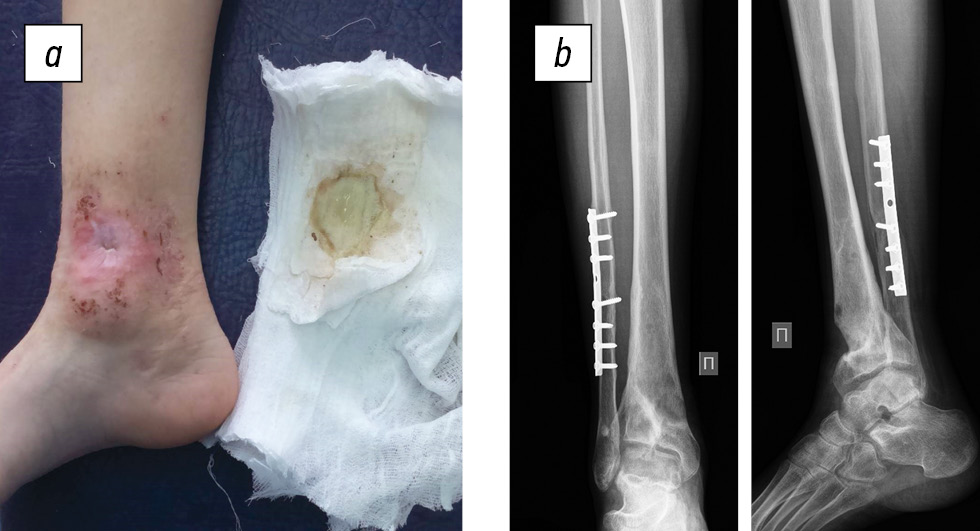

Status localis. The patient walks without aids and limps on the right limb. On the anterior inner surface of the leg in the lower third, a fistula of up to 5 mm in diameter was present, the skin around the fistula (up to 4 cm in diameter) was hyperemic and macerated, with cicatricial changes and scanty serous-purulent discharge (Fig. 4a). Palpation was moderately painful. Toe movement and sensitivity were preserved, and capillary response from the nail plates was brisk. The absolute length of the lower extremities was D < S per 1 cm. X-ray images of the right lower leg revealed a defect in the distal metaphysis of the tibia up to 1/2 the diameter, limited to a zone of sclerosis, proximal to the defect at the level of the metadiaphysis, a heterogeneous bone structure with small cysts, and undefined physeal zone. The fibula fracture consolidation with metal extracortical osteosynthesis was satisfactory (Fig. 4b).

Fig. 4. An 11-year-old female patient diagnosed with chronic post-traumatic osteomyelitis of the right tibia: a, appearance of the limb and the fistulous process; b, radiographs of the right ankle joint in two views